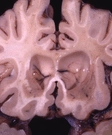

Adrenoleukodystrophy

Adrenoleukodystrophy damages the membrane that insulates nerve cells in the brain. It is linked to X-chromosome and is thus a genetic (hereditary) condition